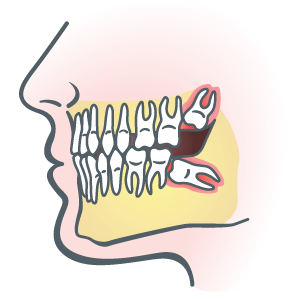

Any tooth has the potential to become impacted—that is, emerge in some oddball direction that crowds other teeth. But the most famous culprits are third molars, the last-to-emerge wisdom teeth.

Not many mouths can accommodate these teeth. They often wind up pressing against their neighbors, ultimately pressuring the rest of the teeth to disrupt their alignment.

Wisdom teeth get our attention when they cause pain and swelling. Routine X-rays, beginning around age 12, alert us to problem potential before wisdom teeth start getting disruptive. X-rays can let us know whether those mighty molars must go.